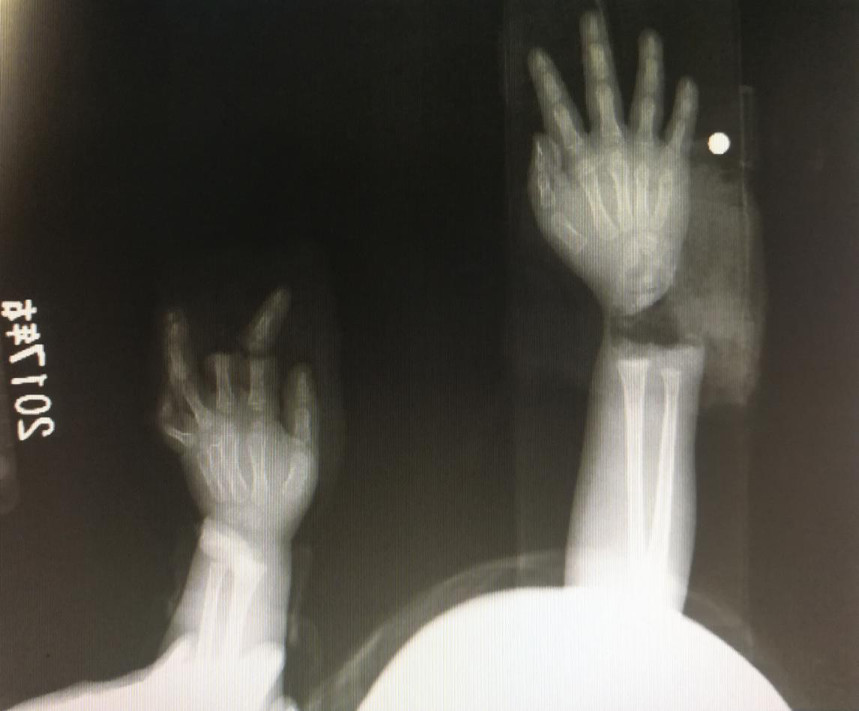

“急診在哪,急診在哪”,伴隨著一聲聲急促的問詢,一位年輕女士抱著渾身是血的小孩疾步前往急診室,懷里的小孩在疲憊與疼痛的交織下,時睡時醒。鑒于小孩的情況,急診醫(yī)生迅速安排給小孩拍了X光片,影像片結果顯示小孩左手手腕完全離斷,右手中、食指離斷,距離事發(fā)時間已經3個多小時,需盡快安排手術。

經過長達5個多小時的手術,小宇(化名)終于被送出了手術室,離斷的手腕和手指均已完成再植,但關于斷指的存活與否還需要經過一個十天的觀察期。小宇的主治醫(yī)生是長沙年輪骨科醫(yī)院手足外科馬思成醫(yī)生,據馬醫(yī)生介紹,小宇受傷情況比較嚴重,失血過多,而且兩個手都存在完全離斷的情況,手術時安排了兩組醫(yī)生同時進行,整個手術過程比較順利,目前小宇還處于觀察期。